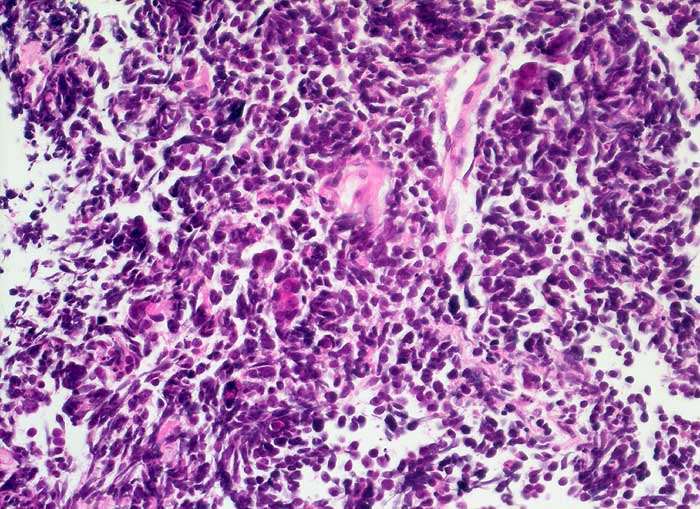

Kleinzelliges Bronchuskarzinom

Der Nachweis des kleinzelligen Karzinoms gelingt im Sputum meist leichter als im Bronchialsekret. Im Bronchialsekret sind die Tumorzellen oft zwischen Flimmerzellen und Entzündungszellen versteckt, während die stark hyperchromatischen Kerne im Sputum schon bei schwacher Vergrösserung ins Auge fallen. Die fast nacktkernigen Zellen liegen einzeln oder bilden schmale zeilenförmige Verbände und Haufen. Innerhalb der Verbände schmiegen sich die Kerne eng aneinander (=molding). Die Kerne sind zwei- bis dreimal so gross wie Lymphozyten. Im Sputum erscheinen die Karzinomzellen kleiner als im Feinnadelpunktat, Bürstenabstrich oder Bronchialsekret.

Basalzellen sind monomorpher und bilden kleine, regelmässige kompakte Verbände. Lymphomzellen liegen stets einzeln. Feindisperse Chromatinverteilung und zeilenförmige Verbände sprechen gegen ein Lymphom. In Zweifelsfällen erfolgt die Unterscheidung immunzytochemisch (Panzytokeratin und CD45).

Das ersten Beispiel zeigt ein Bronchialsekret, das zweite eine Bronchialbürstenzytologie.